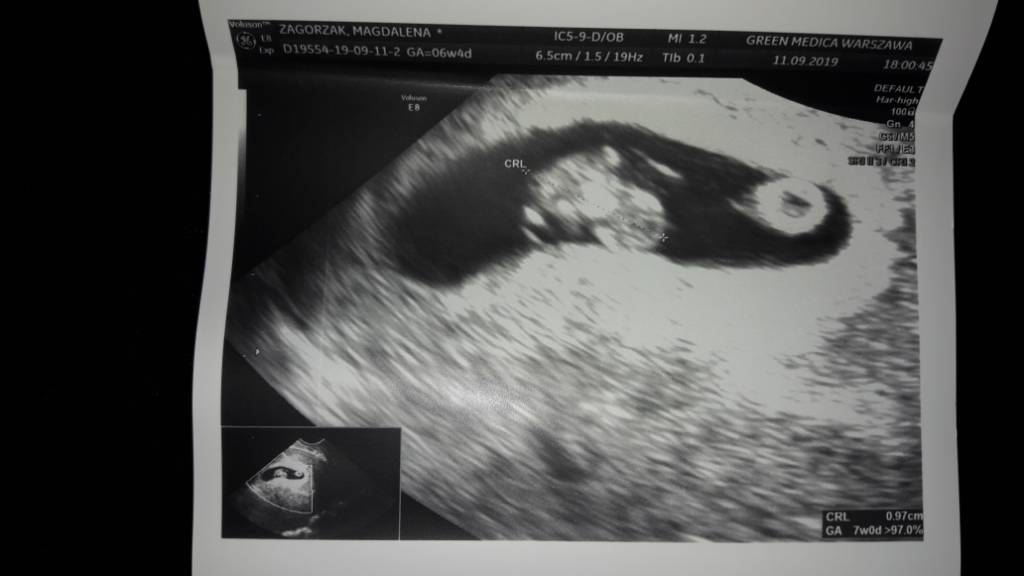

a z tego cos odczytacie? 7tc

20190911_215306.jpeg